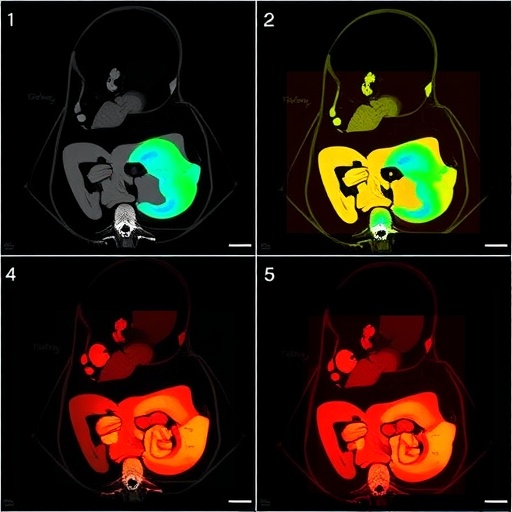

To complement these imaging techniques, computed tomography (CT) is also explored within the study. Although CT scans expose patients to radiation, its capacity to provide exceptional cross-sectional images can be invaluable in specific clinical scenarios. The study raises awareness about the judicious use of CT, aiming to balance the need for accurate diagnosis against the potential risks involved, particularly when managing a vulnerable pediatric population.

The imaging findings presented in the study are not merely academic; they reflect real patient cases with diverse presentations of MMIHS. These cases emphasize the variability in features and the challenges faced during diagnosis. The pictorial review serves as a visual educational tool for healthcare professionals, promoting awareness and understanding of this syndrome.